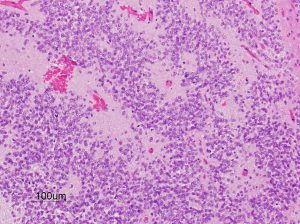

第4脳室床に発生した典型的な上衣腫 EPN-PFA の画像です。水頭症になって,頭痛と嘔吐,意識障害で発症しました。典型的なMRI画像と病理所見です。MRIでは第4脳室からマジャンディー孔を越えて脊髄背側まで長く腫瘍が伸びています。腫瘍内部に小さなのう胞が複数みられます。病理像では,血管周囲に細胞核がない無核野が認められます。血管周囲に伸びた繊細な単極性突起が集まった領域です。これは,血管周囲偽ロゼット perivascular pseudorosette という上衣腫に特徴的な病理所見です。

グレード2の組織像です。血管周囲に無核野があり,腫瘍の核は血管から離れているパターンが特長です。perivascular pseudo-rosetteといいます。